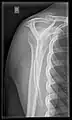

Other axial skeleton

Whole-body radiograph of a major trauma case (where, however, full-body CT scan is usually preferable), showing bilateral femur fractures.[16]

• Cervical spine: The standard projections in the UK AP and Lateral. Peg projection with trauma only. Obliques and Flexion and Extension on special request.[15] In the US, five or six projections are common; a Lateral, two 45 degree obliques, an AP axial (Cephalad), an AP "Open Mouth" for C1-C2, and Cervicothoracic Lateral (Swimmer's) to better visualize C7-T1 if necessary. Special projections include a Lateral with Flexion and Extension of the cervical spine, an Axial for C1-C2 (Fuchs or Judd method), and an AP Axial (Caudad) for articular pillars.